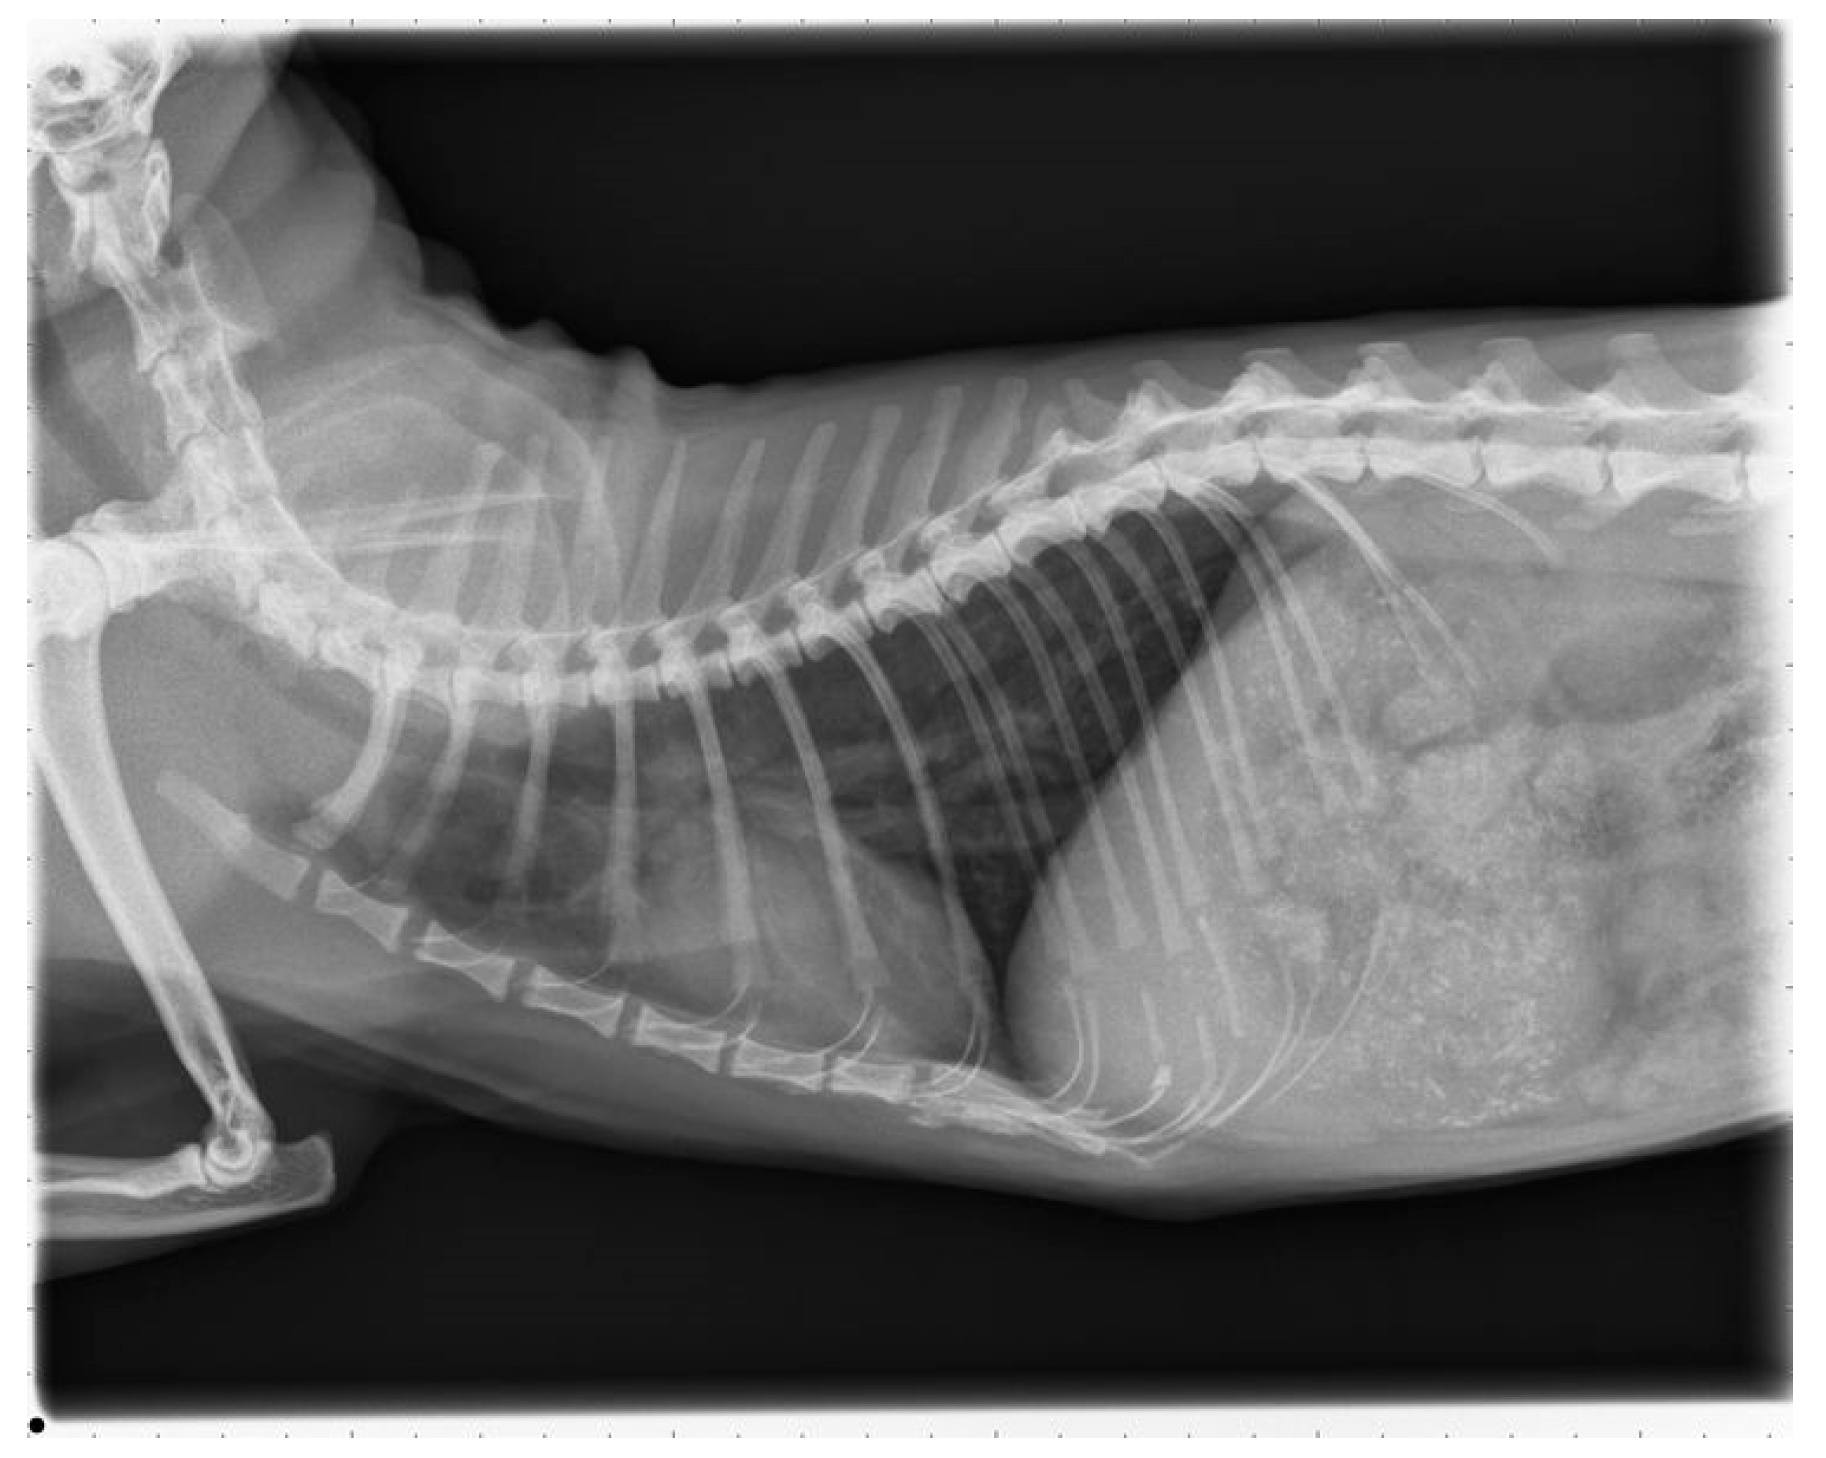

The pretreatment by the referral vet included Benazepril 0.4 mg/kg once daily and Furosemide 1.6 mg/kg twice daily with no improvement of clinical signs. The referral vet also took thoracic and abdominal radiographs. The thoracic radiographs showed a diffuse bronchointerstitial pattern of the pulmonary parenchyma with enlarged pulmonary arteries. The abdominal radiographs revealed decreased delimitation of the abdominal organs—most likely due to ascites.

2.6. Follow Up

The cat was presented 16 months after surgery for a control examination including thoracic radiographs and echocardiography at the Veterinary Hospital in Parndorf, Burgenland. The owner reported that the cat was not showing any clinical signs despite of infrequent, spontaneous coughing and receiving the prescribed medication daily. Clinical examination remained unremarkable. The thoracic radiographs showed a moderate bronchointerstitial lung pattern without enlarged pulmonary arteries (Figure 7). This bronchointerstitial lung pattern could be due to heartworm associated respiratory disease (HARD).

Figure 7. Thoracic radiograph, right laterolateral view.